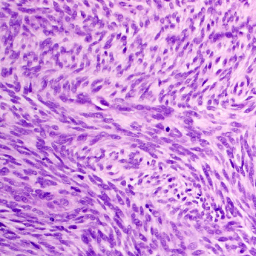

Отчет по первой химии, трехдневная схема AI (доксорубицин + ифосфамид), локоть, синовиальная саркома.